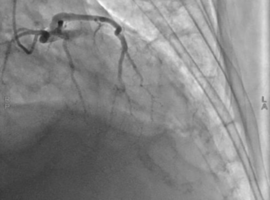

Citation: Yılmaz S, Kandemir HC, Kıtlık EB. Right Coronary Artery Post-stenotic Giant Saccular Aneurysm that is Managed by Graft Stenting after Revascularization of Aneurysmatic Lad Lesion for Acute Anterior STEMI. Case Rep Clin Cardiol J. 2026; 6(2): 176.